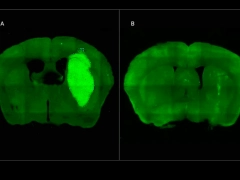

A) Tumor cerebral en modelo preclínico. B) Tumor desaparece con estrategia terapéutica

A) Tumor cerebral en modelo preclínico. B) Tumor desaparece con estrategia terapéutica Foto: NA